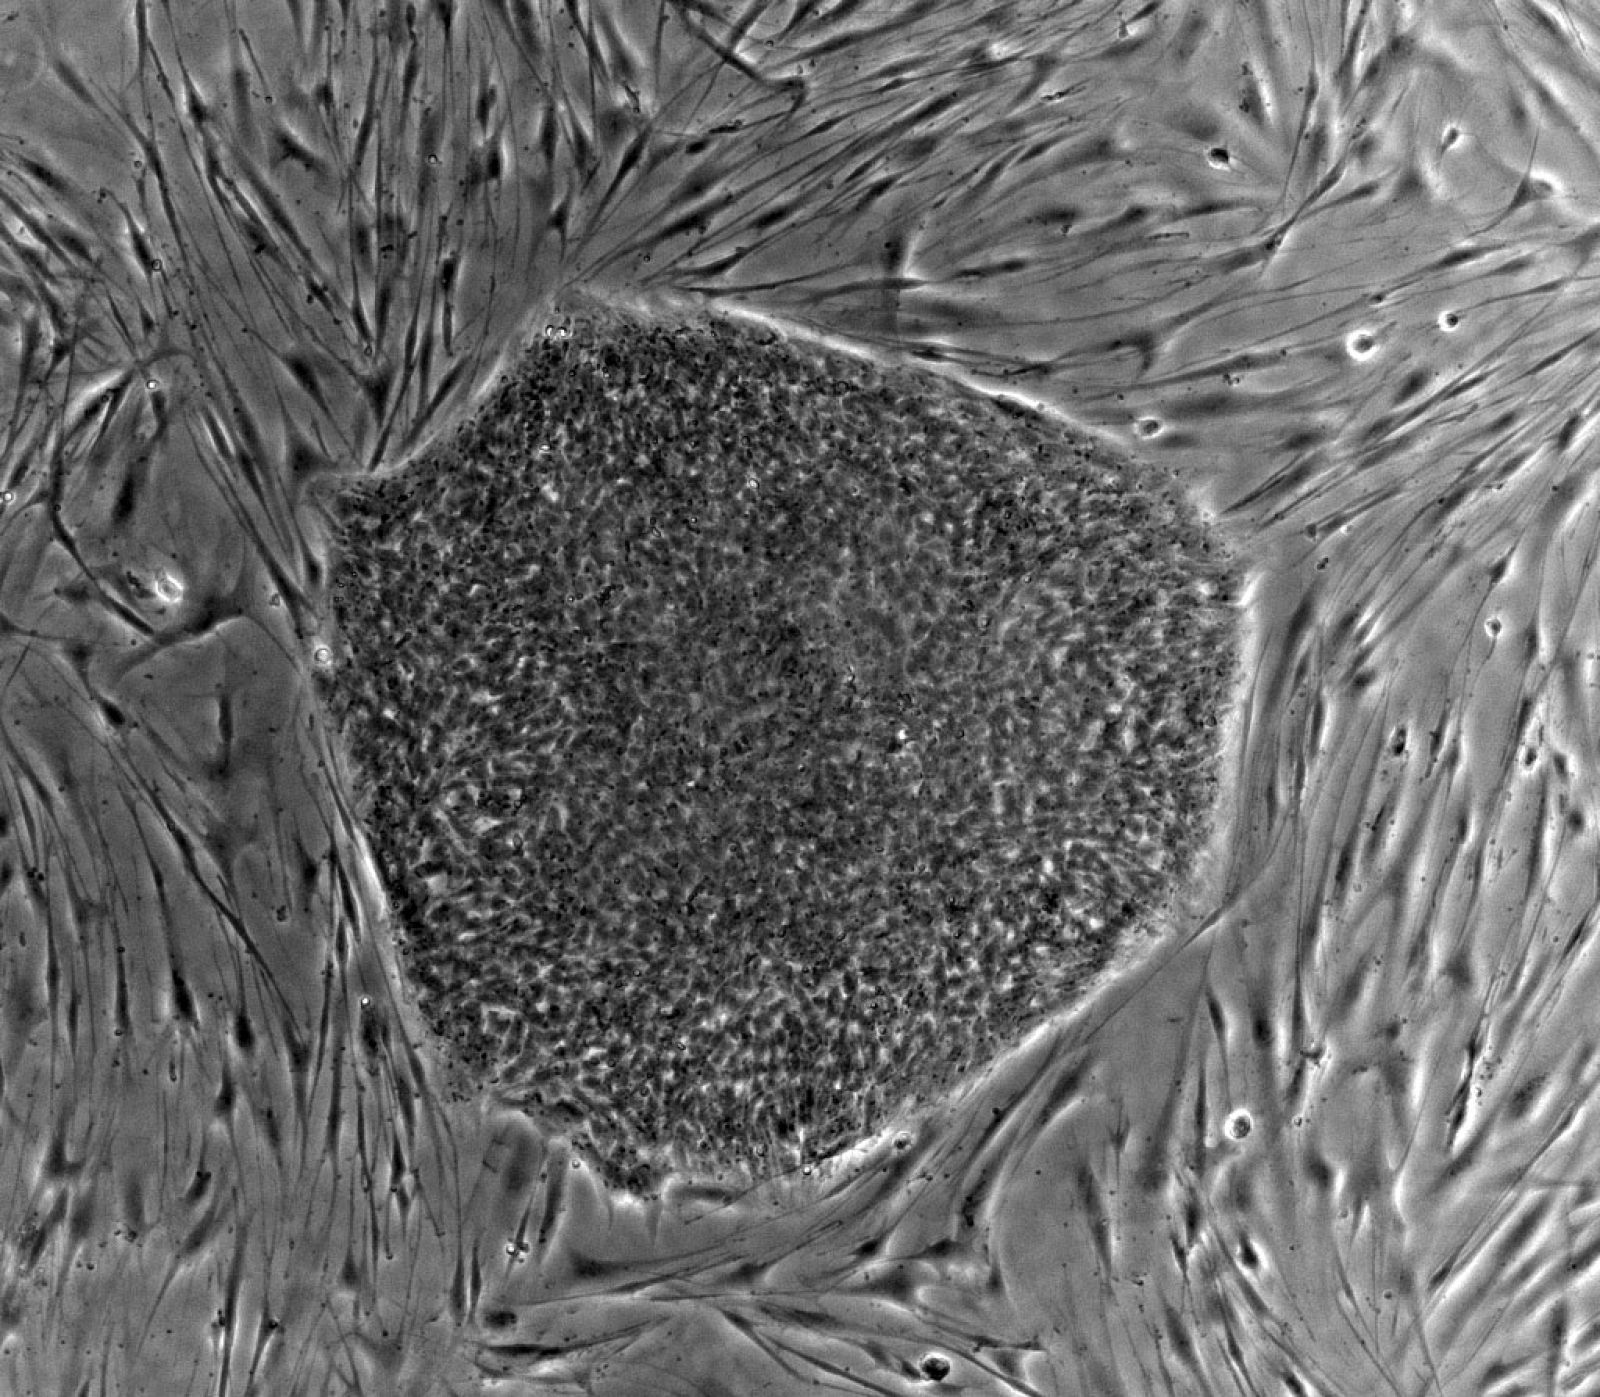

El investigador Joan Massagué ha anunciado este lunes que han descubierto que la metástasis del cáncer de mama podría evitarse atacando la proteína SRC, una pieza vital en la alimentación de las células cancerosas letales que durante años se alojan en estado latente en órganos vitales, antes de manifestarse.

El científico ha explicado, además, que hay un medicamento en el mercado, que se utiliza para tratar la leucemia mieloide crónica cuando fracasa el primer tratamiento, que actúa contra la proteína SRC, lo que significa que "si se elimina esta pieza se corta el suministro a estas células latentes malignas para que vivan".

El científico ha recordado que la metástasis es lo que dificulta a los médicos el tratamiento del cáncer y que el 90% de los fracasos se debe precisamente a que a partir del tumor primario hay una invasión de células distantes que no se logran eliminar con los tratamientos actuales, y que al cabo de años, incluso décadas, consiguen hacer colonizaciones metastásicas en órganos vitales.

En su discurso ha insistido en que cuando se inicia un tumor cancerígeno, y antes de que se diagnostique, ya hay células tumorales que viajan a través de la circulación sanguínea a otros órganos, y que aunque el 99,99% de ellas mueren por condiciones extremas, unas pocas vivirán y lograrán infiltrarse en los pulmones, el hígado, el cerebro o en el riñón para reaparecer más tarde.